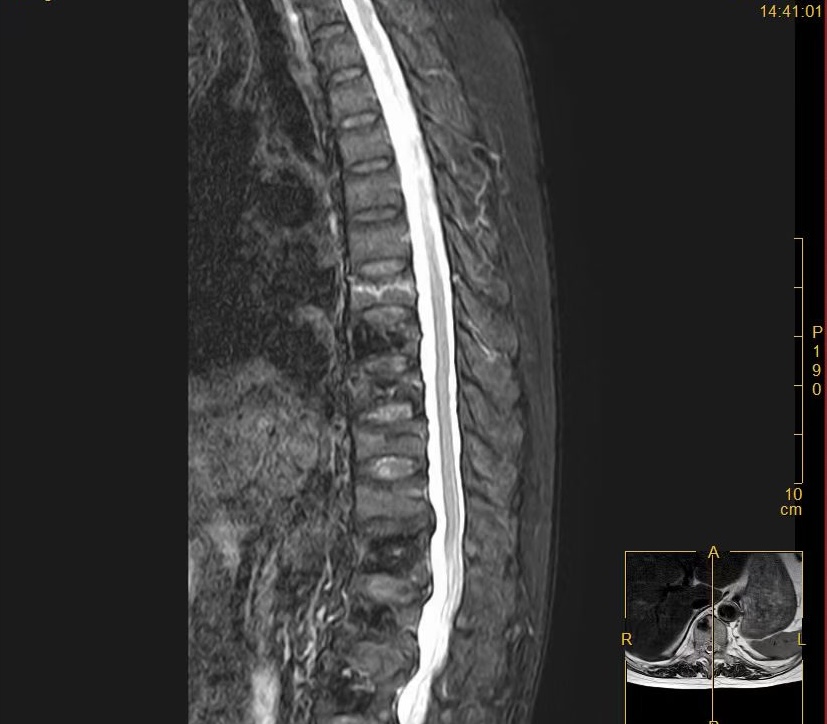

术前MR

“做完手术就能下床走路,真是太感谢你们了!” 近日,在我院骨一科病房,赵奶奶握着医护人员的手,激动地说道。赵奶奶是一位重度骨质疏松患者,近年来饱受腰背疼痛的折磨,曾多次来我院接受骨水泥治疗。近日,赵奶奶不慎闪腰,导致胸背部剧烈疼痛,难以忍受,遂来我院骨一科就诊。经检查,赵奶奶被诊断为胸7椎体压缩性骨折。